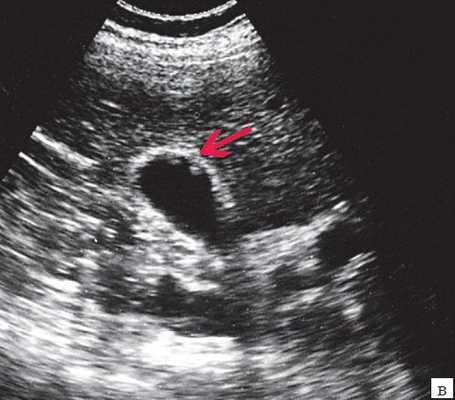

- Ультразвуковая диагностика. К визуализирующим методам диагностики холангита относятся УЗИ брюшной полости и печени, ультрасонография желчных путей. С их помощью удается получить изображение желчных протоков, выявить их расширение, определить наличие структурных и очаговых изменений в печени.

Инструментальная диагностика

В первую очередь пациентам с подозрением на холедохолитиаз проводят ультразвуковое исследование желчевыводящей системы, причём его используют на протяжении всего периода болезни, чтобы отследить динамику лечения. УЗИ помогает оценить состояние протока поджелудочной железы, показывает ворота печени и забрюшинное пространство. Иногда ультразвуковое исследование не позволяет рассмотреть камни в желчном протоке из-за вздутия кишечника, толстой передней брюшной стенки или скопления различных веществ в области ворот печени. Однако в 90 % случаев УЗИ справляется со своей задачей. В некоторых случаях УЗИ также помогает дифференцировать холедохолитиаз и опухоли в печени, желчном пузыре и протоках [7] [8] [9] .

Наибольшей популярностью среди современных методов исследования пользуется эндоУЗИ — высокоточный метод, который сочетает в себе возможности эндоскопической и ультразвуковой диагностики. Он позволяет выполнять детальную ультразвуковую диагностику с последующим забором тканей для их исследования на клеточном уровне. УЗИ проводят с помощью гибкого эндоскопа со стороны просвета двенадцатиперстной кишки [21] [23] [25] [27] .